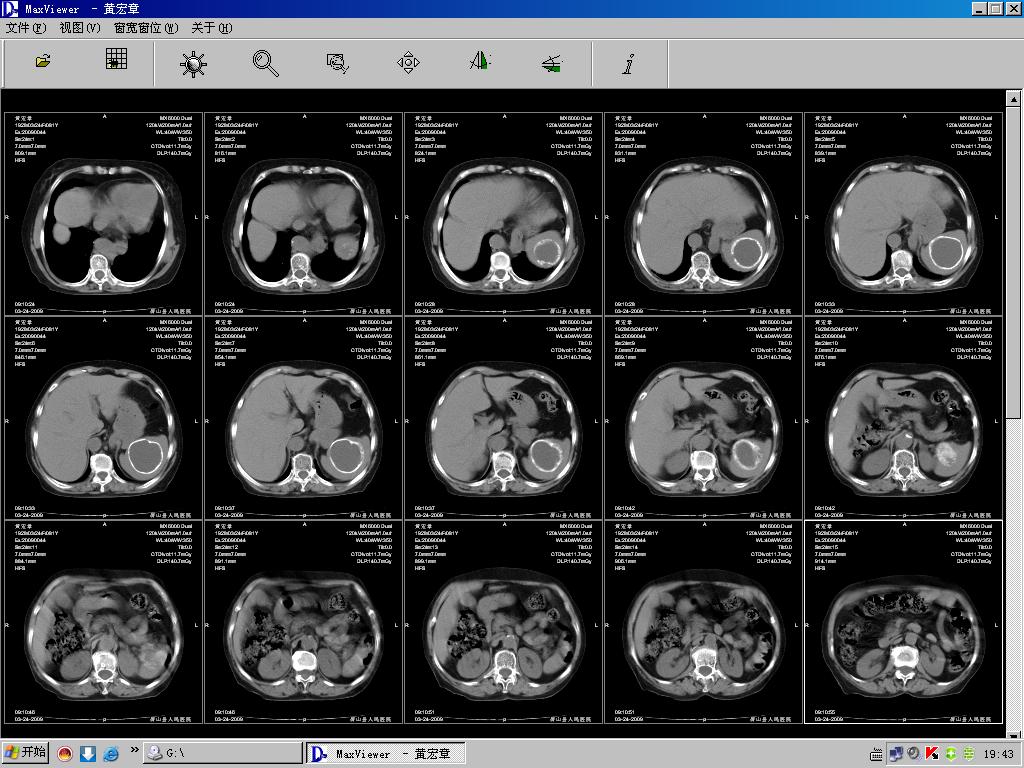

病人女,81岁,临床以呕血为主诉!请大家帮忙分析!

1、ct征象:脾实质内可见一类圆形囊性病变,其壁呈连续完囊钙化,病变内密度均一,病变与正常脾实质界限清楚。

2、诊断:首先考虑脾内良性囊性占位,包虫可能性大,不完全排外脾囊肿。(包虫囊肿壁钙化机率相对高,而单纯囊肿壁可以钙化,而完全钙化的少见)。

非寄生虫囊肿大多为脾外伤后血肿退变的结果,也可见于脾梗死后ct表现单发或多发圆形、类圆形低密度影,境界清楚,壁菲薄,偶尔可伴有钙化,增强扫描无强化。形成过程是外伤引起脾脏的血肿,血肿被包裹,血液被吸收,周围形成纤维性囊壁,囊液不断蓄积,逐渐形成浆液性孤立性囊肿,囊肿可以很大,囊壁无内皮细胞被覆,其内常含血液,一般可追逐到外伤史,晚期可发生钙化。本例最为符合。